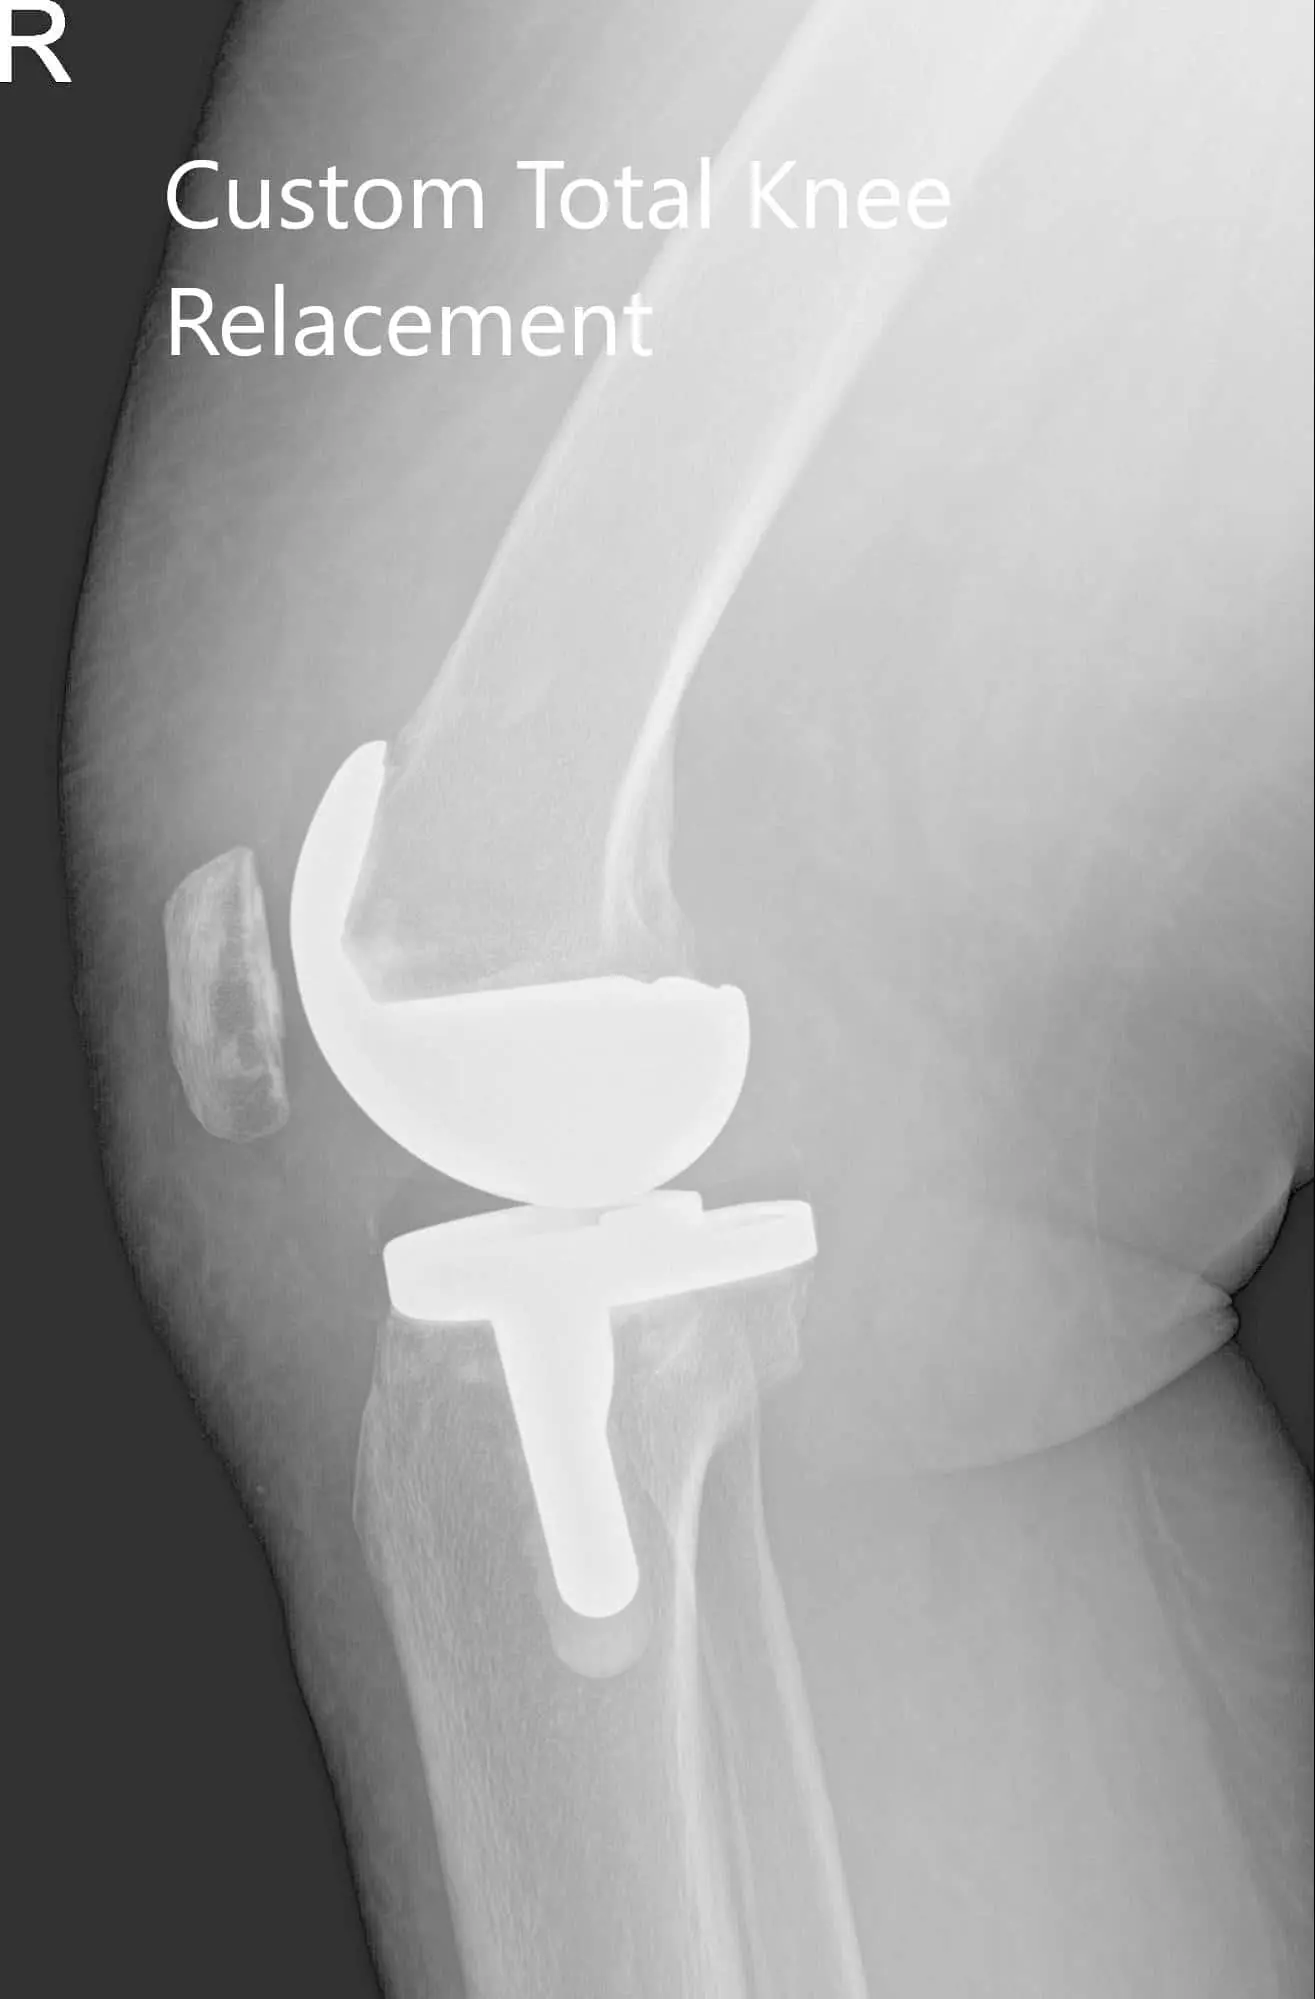

Postoperative X-ray of the patient’s right knee showing AP and lateral views

Implants used: 8 mm posterior stabilized polyethylene with tibial tray, femoral implant 32 mm,

6 mm thickness polyethylene with an 8 mm polyethylene insert.